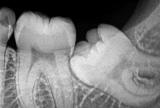

Всем известно, что у человека могут образоваться зубы мудрости. Они обычно появляются во взрослом возрасте. Болезненные прорезывания часто оборачиваются удалением. Но зачем вообще нужны зубы мудрости и нужно ли удалять их...